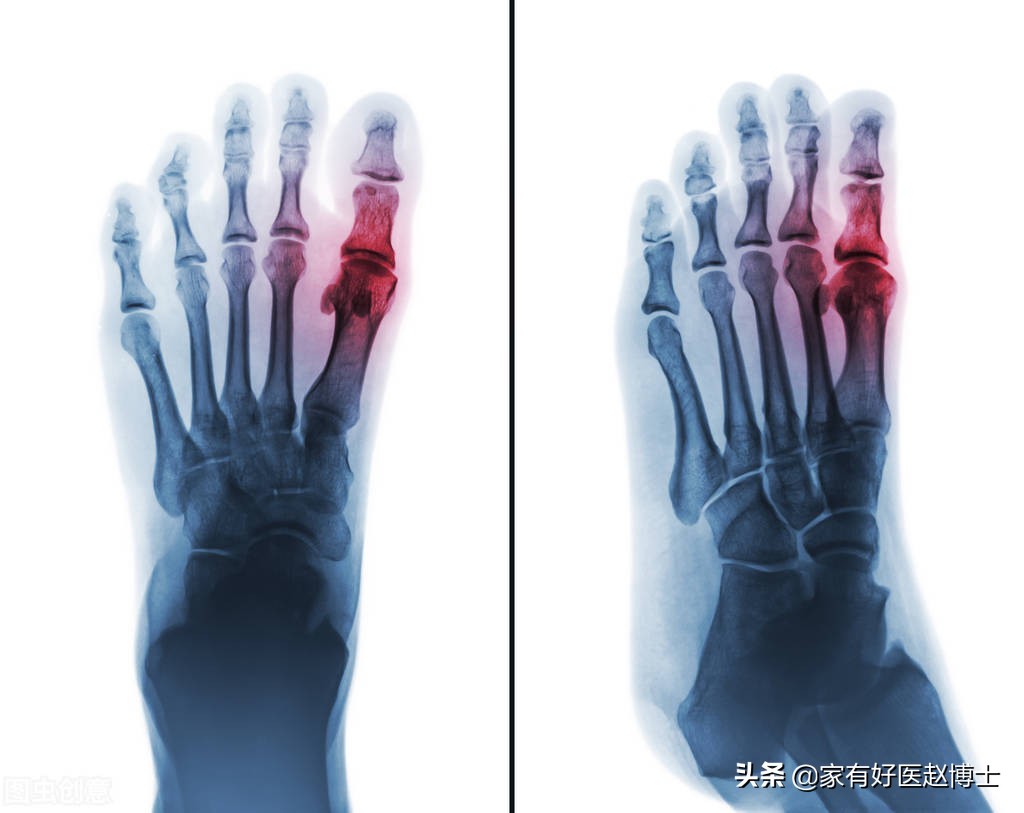

一说起血液当中尿酸水平升高,很多人会直接联想到痛风。

但事实上,并不是所有高尿酸的人群都会发生痛风。有高尿酸但长期不发作痛风,这被称为“无症状高尿酸”。

而高尿酸究竟何时需要使用降尿酸药物,其实关键就是看有没有痛风发作。

2019版《痛风及高尿酸血症基层诊疗指南》告诉我们,有两种情况建议直接启动降尿酸药物治疗:

第一, 是每年痛风(痛风性关节炎)的发作次数≥2次;

第二, 是每年痛风(痛风性关节炎)只发作1次,但是检查发现有明显的痛风石、泌尿系统结石又或者慢性肾脏疾病已达3期以上。